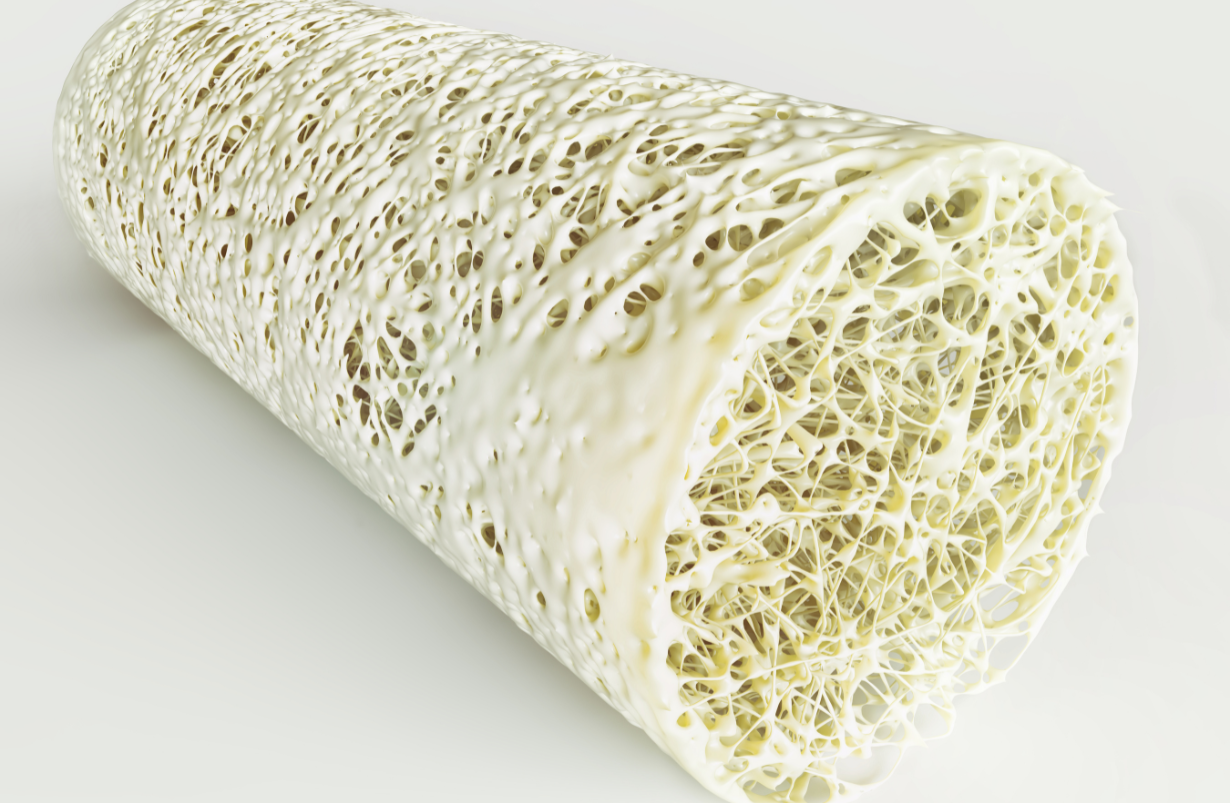

Kyphosis

DEFINITION: Exaggerated or extreme forward (ventral) bending usually of the thoracic spine. It is often caused by aging with poor posture, but may also be due to wedge fracture(s) of the front (anterior) portion of the vertebral body(ies), itself a frequent sequel to osteoporosis. BENEFICIAL POSES: Utkatasana with lumbar spine and back of head against a wall, Salabhasana, Uttana Padasana. EXPLANATION: Utkatasana with a wall prompts awareness of which muscles need to be coordinated for better posture. Salabhasana and Uttana Padasana strengthen the paraspinal muscles required to reduce kyphosis. REFERENCE: Greendale GA, Huang MH, Karlamangla AS, Seeger L, Crawford S.Yoga decreases kyphosis in senior women and men with adult-onset hyperkyphosis: results of a randomized controlled trial. J Am Geriatr Soc. 2009 Sep;57(9):1569-79. doi: 10.1111/j.1532-5415.2009.02391.x. Epub 2009 Jul 21.

Osteoporosis

Reduction of bone mineral density below the level found in 99% of healthy 25 - 30 year old women. BENEFICIAL POSES: The most successful efforts so far use Vriksasana, Trikonasana, Parsvakonasana, Virabhadrasana II, Parivrtta Trikonasana, Salabhasana, Setu Bandhasana, Marichyasana III, Matsyendrasana, and Supta Padangusthasana I and II. EXPLANATION: Wolff's law states that "the architectonic of a bone follows the lines of force to which that bone is exposed." Yoga imposes far greater forces than gravity, since muscles that easily oppose gravity when we move are often pitted against one another in yoga, vastly exceeding gravity's pull on those bones. Therefore yoga successfully reverses osteoporosis. The poses should be held for at least 30 seconds. EVIDENCE: Lu, Y-H, Rosner, B, Chang, G, PhD; Fishman, L. “Twelve-Minute Daily Yoga Regimen Reverses Osteoporotic Bone Loss.” Topics in Geriatric Rehabilitation: April/June 2016 - Volume 32 - Issue 2 - p 81–87. Julius Wolff. "The law of bone transformation." A. Hirschwald, Berlin; 1892.

Spinal Fracture (vertebral body)

Spinal Fracture (vertebral body), Compression Fracture

Fracture of the front portion of a vertebral body. Usually in the thoracic or lumbar spine; often from osteoporosis. Often extremely painful for up to 6 weeks, but very rarely causing weakness, numbness or sciatica. BENEFICIAL POSES: Savasana, Salabhasana, Ustrasana, Dhanurasana. EXPLANATION: These extension postures rock the vertebral column back on the facet joints, taking pressure off the front of the vertebral bodies, where this type of fracture almost invariably occurs. REFERENCE: Sinaki M. Exercise for patients with osteoporosis: management of vertebral compression fractures and trunk strengthening for fall prevention. PM R. 2012 Nov;4(11):882-8. doi: 10.1016/j.pmrj.2012.10.008.